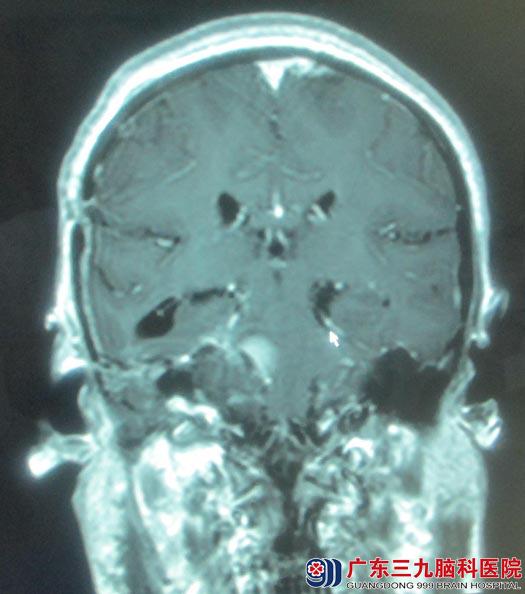

鲁明主任阅片后认为:右侧中后颅窝、延斜区脑膜瘤,目前已对动眼神经、外展神经、三叉神经、面听神经、舌咽神经及副神经造成影响,并与脑干紧密相连,手术风险大。经过周全安排,由鲁明主任主刀,术中取右侧乙状窦后入路,见肿瘤呈灰白色,边界较清,质中,血供丰富。肿瘤供血主要由延斜区硬脑膜动脉参与,岩上窦与肿瘤关系密切,予显微镜下电凝烧灼分离肿瘤基底部供血动脉,分块切除肿瘤。过程中岩上窦及海绵窦均有出血,予明胶海绵压迫止血,肿瘤边缘近包膜区,面听神经、三叉神经、迷走神经、副神经及舌咽神经粘连紧密,在电生理监测下,仔细辨认,小心分离,中后组颅神经均解剖保留,肿瘤内侧面与脑干粘连紧密,为避免脑干损伤导致术后严重功能障碍,予残留部分肿瘤。术中出血少,术后恢复良好,病理结果示:纤维型脑膜瘤(WHO1级)。

手术后

纤维型脑膜瘤是一种比较常见的脑膜瘤类型,该类肿瘤为良性肿瘤,通常血供一般,手术为首选治疗方案。本例患者,肿瘤位于中后颅窝,体积大,与前、中、后组颅神经均有粘连,内侧与脑干粘连,前方侵犯海绵窦,手术难度大,术中容易出现海绵窦、岩上窦等重要静脉系统出血。控制术中出血量、保护颅神经及脑干功能是手术的关键。在切除肿瘤过程中,先处理肿瘤供血动脉,能有效的减少出血;术中电生理监测,在辨认颅神经方面起到重要作用;在切除近脑干区肿瘤时,保护脑干功能至关重要,必要时残留小部分肿瘤,避免术后出现严重功能障碍。本例患者肿瘤大部分切除,剩余小部分肿瘤需进一步行放射治疗。